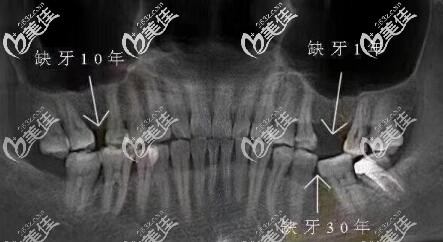

牙齿缺失10多年,旁边牙齿倾斜还能做种植牙修复吗?

下面一颗牙缺失多年,一直没管,现在想整,发现邻牙倾斜了怎么办?还能做种植牙修复吗?

牙齿缺失要及时镶牙、种牙,如果不及时种牙,旁边其它的牙齿会向缺牙方向逐渐倾斜,对面牙齿逐渐伸长。容易食物嵌塞,引起牙周问题,从而导致更多健康牙齿发生问题。

缺牙10多年,想要种植牙修复,此时缺牙部位可能上下和左右间隙都不够,此情况是可以考虑牙齿矫正关闭间隙,或者先正畸,拉开间隙,再做种植牙,具体情况还需要拍牙片。

牙齿缺失不尽快修复,无特殊情况一般半年以后就开始倾斜,随着时间越长倾斜越厉害,邻牙倾斜是个慢化过程,正常情况下个人很难感应到,有些人会有轻微的面部变化。